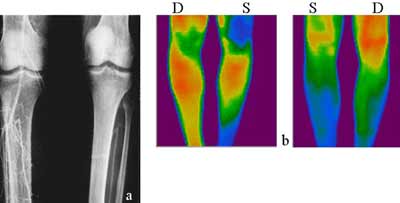

Во всех случаях обтурации передней берцовой артерии от вентральной поверхности голени обнаружилось от умеренного до слабого инфракрасного излучения, степень которого полностью коррелировала с показателями регионального систолического давления по данным УДИ и артериографии. В то же время в дорзальной проекции термографическая картина в ряде случаев почти не отличалась от нормальной (Рис. 3). Напротив, при тромбозе ЗБА обширные гипотермические зоны были установлены в области дорзальной поверхности голени, в то время как почти вся ее передняя поверхность излучала значительно более высокую температуру, при наличии достоверного температурного градиента, достигающего в отдельных случаях 8 градусов (Рис. 4).

Рис. 3. Облитерирующий атеросклероз. (а) Ангиография. Облитерация передней берцовой артерии правой голени, задняя берцовая артерия проходима. (б) Гипотермия всей вентральной поверхности правой голени.ТБИ 0.28. (с) По дорзальной поверхности той же голени гипотермия отмечается только в дисталной ее трети. ТБИ 0.43.

Рис. 4. Облитерирующий тромбангит. (а) Артериография. Непроходимость левой бедренной и подколенной артерии. Задняя берцовая артерия облитерирована тотально на левой и в нижней трети на правой голени. Передняя берцовая артерия проходима на левой и облитерирована в дистальной трети правой голени. (б) Термография. Нормальная вентральная термограмма правой и умеренная гипотермия нижней трети левой голени. Гипотермия дорзальных поверхностей обеих голеней, более выраженная слева. ТБИ на правой ПБА 0.60, на левой 0.51. ТБИ на правой ЗБА 0.48, на левой 0.32.